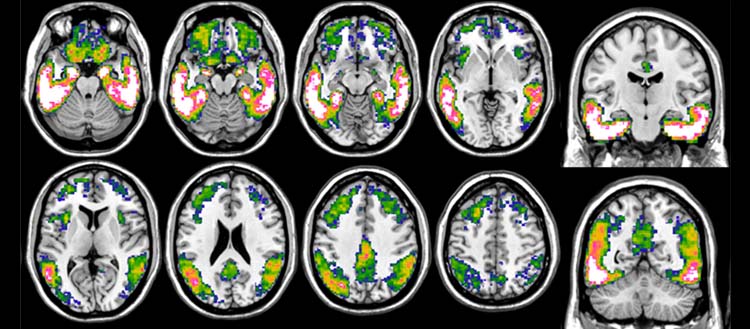

© UNIGE. Imagerie de la tau avec le 18F-Flortaucipir PET dans la maladie d'Alzheimer. La figure montre un modèle prototypique d'accumulation de tau, obtenu en comparant la charge en tau de patient-es atteint-es de la maladie d'Alzheimer à celle de témoins sain-es. L'échelle de couleur bleu-blanc indique des charges de tau plus prononcées, les zones rose-blanc représentant celles où l'accumulation est la plus importante.

Le Flortaucipir est un radiotraceur se liant à la protéine tau mis au point par une compagnie pharmaceutique et approuvé en 2020 par la Food and Drug Administration (FDA). Il permet d’observer son accumulation dans le cerveau, et surtout sa distribution, et d’évaluer précisément son rôle dans la manifestation clinique de la maladie.